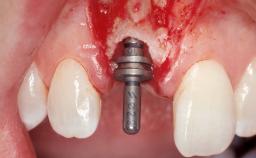

Early Placement of an Implant in a Maxillary Right Central Incisor Site

This 41-year-old female patient was referred to the clinic for the replacement of the right central incisor, since the tooth had developed a root fracture in the long axis that made extraction necessary. The healthy, non-smoking patient was first seen with the tooth still in place. A detailed Esthetic Risk Assessment was performed.The patient was worried about her dental esthetics and had high expectations for a successful treatment outcome from an esthetic point of view. The patient had a medium lip line that displayed parts of the gingiva in the anterior maxilla upon smile.

Bone Augmentation Horizontal|Simultaneous

Augmentation Materials Autogenous chips|Xenogenous|Membrane

Bone Volume Deficient horizontally, allowing simultaneous augumentation